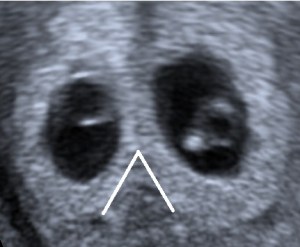

In twin pregnancies prenatal diagnosis of chorionicity is important because chorionicity rather than zygocity is the main factor determining pregnancy outcome. An important feature of dichorionicity is the extension of placental tissue into the base of the inter-twin membrane. This sign has been named the Lambda sign and is typically used at 10-14 weeks (Sepulveda et al., 1996).